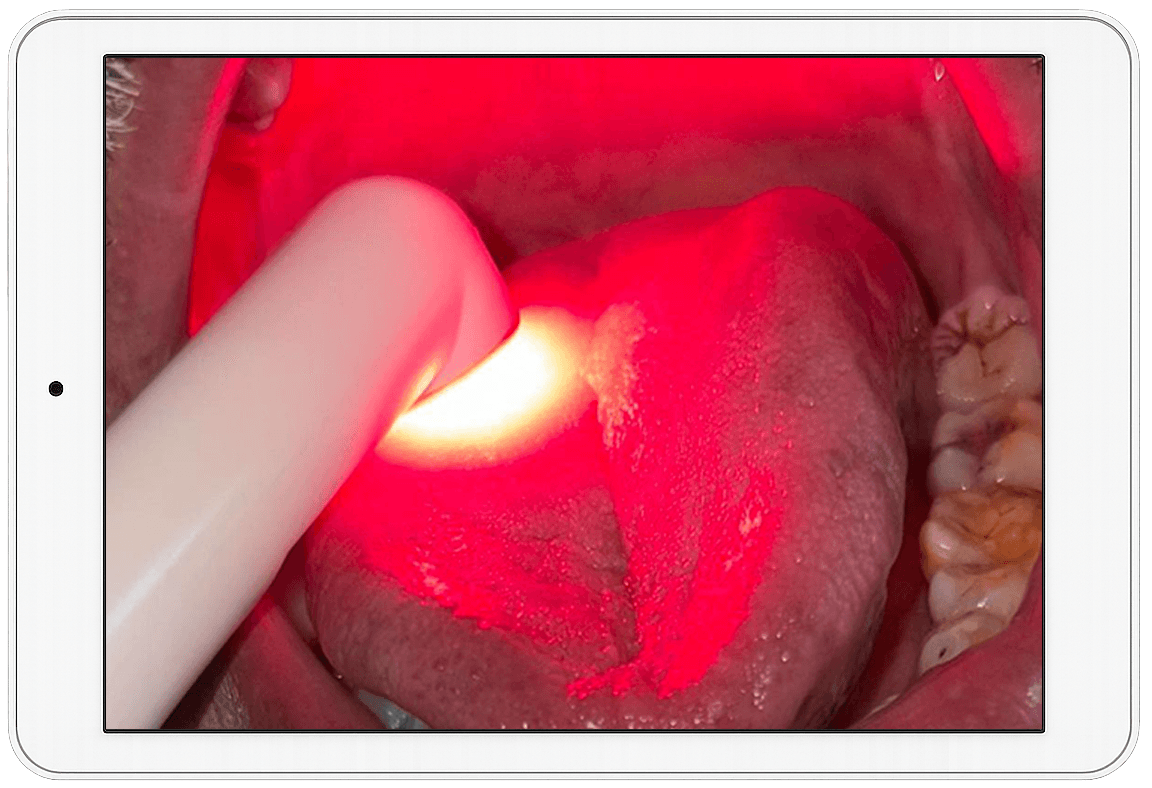

From 'REAL' Patient video repository to weekly 'LIVE' expert sessions as well as Laser Safety Officers' (LSO) certification, LaserPRO supports every step of your dental laser practice. Perfect for enhancing precision, esthetics, and patient outcomes.

LaserPRO by the Asian Academy of Laser Therapy is the ultimate mobile companion for advancing laser education. It offers instant access to a comprehensive e-library, weekly 'LIVE' sessions led by industry experts, and a unique video repository of 'REAL' patient cases. You can instantly access digital classes as per the curriculum set for Associate Fellowship (10 Digital Self Paced Modules) as well as join the Weekly 'LIVE' study club sessions with renowned international experts from ILS (International Laser Specialists). You can also complete your Laser Safety Officers' training and certification directly through the app. Whether you're brushing up on knowledge or taking your first steps in laser dentistry, LaserPRO brings it all to your fingertips! It's Laser Learning made Smarter, Faster and more accessible than ever!